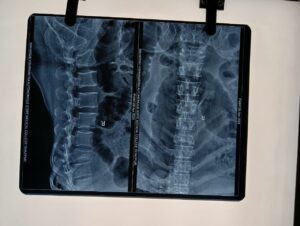

गाजीपुर। महर्षि विश्वामित्र मेडिकल कालेज के हड्डी रोग विशेषज्ञों द्वारा एक और कीर्तिमान स्थापित किया गया। शनिवार को मेडिकल कालेज के आपरेशन थियेटर में 75th वो स्पाइन का सफल आपरेशन किया गया वो भी वहुत ही कम खर्च में, मरीज बृजमा, उम्र-35 वर्ष, मोहल्ला- माक्तपुरा, तुलसिया का पुल, गाजीपुर की निवासी है जो कुछ दिनों पहले मेडिकल कालेज को हड्डी रोग विभाग में इलाज कराने आयीं थीं इलाज करने वाले डा० अवनीश में जांच में पाया कि उनक रिढ़ की हड्डी में फ्रेक्चर है, उन्हें भर्ती किया गया, मरीज की आंर्थिक स्थित को देखते हुए बहुत ही कम खर्चा में यहाँ की टीम (हड्डी रोग विभाग) ऑपरेशन करने की ठानी ताकि मरीज को आराम मिल सकें और आज वह दिन था जब यह कीर्तिमान स्थापित हो गया। ऑपरेशन की टीम में डॉ. अवनीश मिश्रा, विभागाध्यक्ष, (विभागाध्यक्ष हड्डी रोग विभाग) डॉ. रोहित पटेल (एसोसिएशन प्रोफेसर) डॉ. शेखर आजाद (हड्डी रोग विशेषग), निश्चेतन विभाग से डा० आर० के मिश्रा, डा विवेक विवेक उपाध्याय और समस्त ओटी स्टाफ मौजूद रहे। मौके पर मेडिकल कालेज के प्रिंसपल डॉ आनन्द मिश्रा ने पूरी टीम को बहुत-बहुत बधाई दी और इसी तरह समाज के प्रति अपने कर्तव्यों का निर्वहन करने के लिए प्रशंशा की। गाजीपुर मेडिकल कालेज भी किसी मामले में कम नहीं है हर तरह की सुविधाए मरीजों के लिए उपलब्ध है और लगभग हर छोटी-बडी सर्जरी अब यहां होती है। अन्यथा मरीजो को बनारस जाकर महीनो का इन्तजार करना पड़ता था।